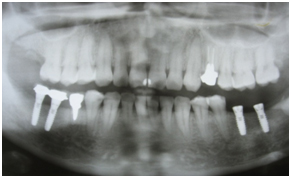

患者さん:女性

主訴:入れ歯が合わないのでインプラントをいれてほしい

所見:両側遊離端欠損

右下臼歯部は以前に埋入済み 左下67番に埋入予定

左下にプラトンインプラントφ3.7×10mmを2本埋入